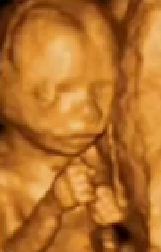

28 Haftalik Gebelikte 6 5 Aylik Anne Karnindaki Bebege Ait 4 Boyutlu U Bebek Ultrason Videolar Anne